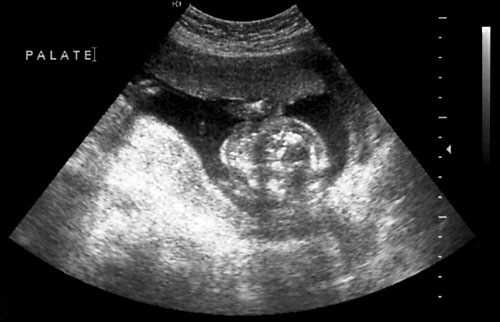

- Views through axial plane to note palate/tooth buds.

Normal transverse view of palate at 18 weeks at level of tooth buds (left, at arrow). Normal fetal orbits seen to left of arrow in photo (middle). Normal ear just for fun (right)!